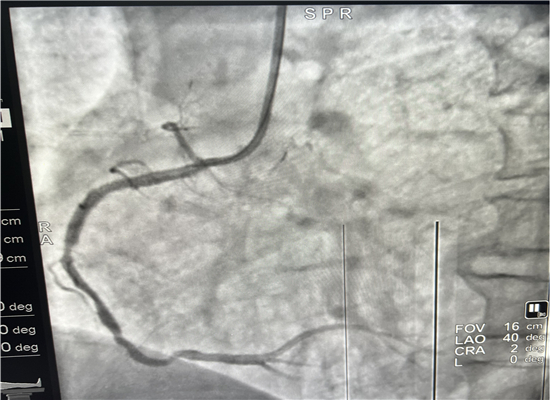

杨勇主任、张轩副主任进行介入手术操作

早上8时48分,120急救中心接到六麻卫生院的出诊电话,有一名胸痛病人7时左右在家晕倒,家属急送到六麻卫生院,初诊为急性心肌梗塞,病情危重,需马上转院到我院进一步治疗。急诊医学科立即启动急性心肌梗塞救治绿色通道预案,立即出车,于9时40分到达六麻卫生院,到诊后复查心电图并立即上传微信群会诊,确诊后为患者按急性心肌梗死急诊介入治疗做准备,监护返回。提前通知心血管内科医师到急诊医学科等侯会诊,并同时激活导管室。10时45分患者顺利转运回我院,心内科医师会诊后快速完成知情谈话及签字,10时57到达导管室,由杨勇、张轩两位主任进行介入手术,术中发现患者右冠状动脉100%闭塞,11时46分顺利植入一枚支架,患者的心肌得以重新灌注,11时58分手术结束,术后患者胸痛症状明显缓解,12时12分转到CCU监护。